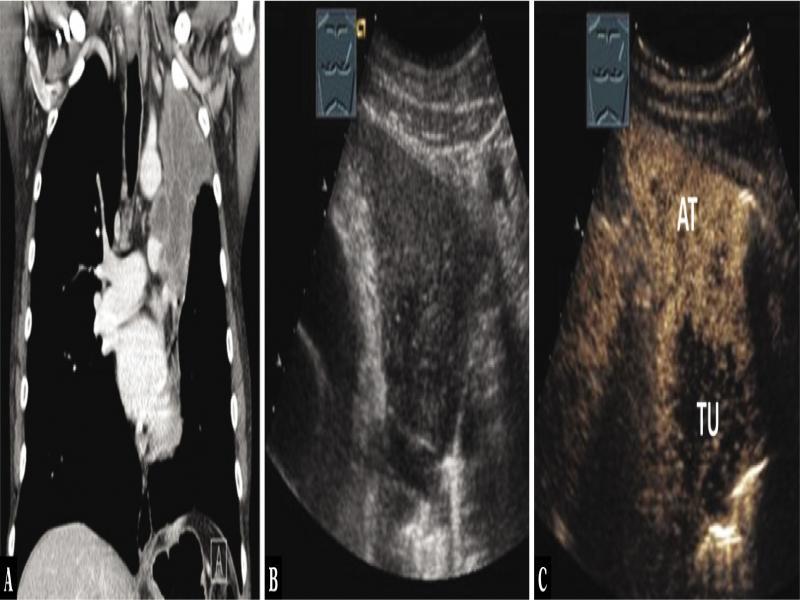

Fig. 9.

A 46-year-old male patient with thoracic pressure and mediastinal tumor in the anterior mediastinum on computed tomography (A). Thoracic ultrasound indicated homogeneous low echo consolidation (B), which shows mixed central reduced enhancement on contrast-enhanced ultrasound. Here, the central tumor (TU) demarcates from the atelectasis (AT) (C). Transatelectatic ultrasound-guided biopsy was performed, and the diagnosis of bronchial carcinoma was confirmed histologically